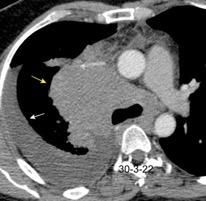

Síndrome de afectación postcardiaca (postcardiac injury)

Post infarto 1-7 % (Dressler)

Trauma cerrado Implantación marcapasos

Cirugía cardiaca. 17-31% (Post.pericardiotomía)

3707 pacientes 29 Derrames (0,78%) > de 25% del hemitórax

Todas menos 2 Izdos.

Angioplastia

By-pass coronario 21-10-03